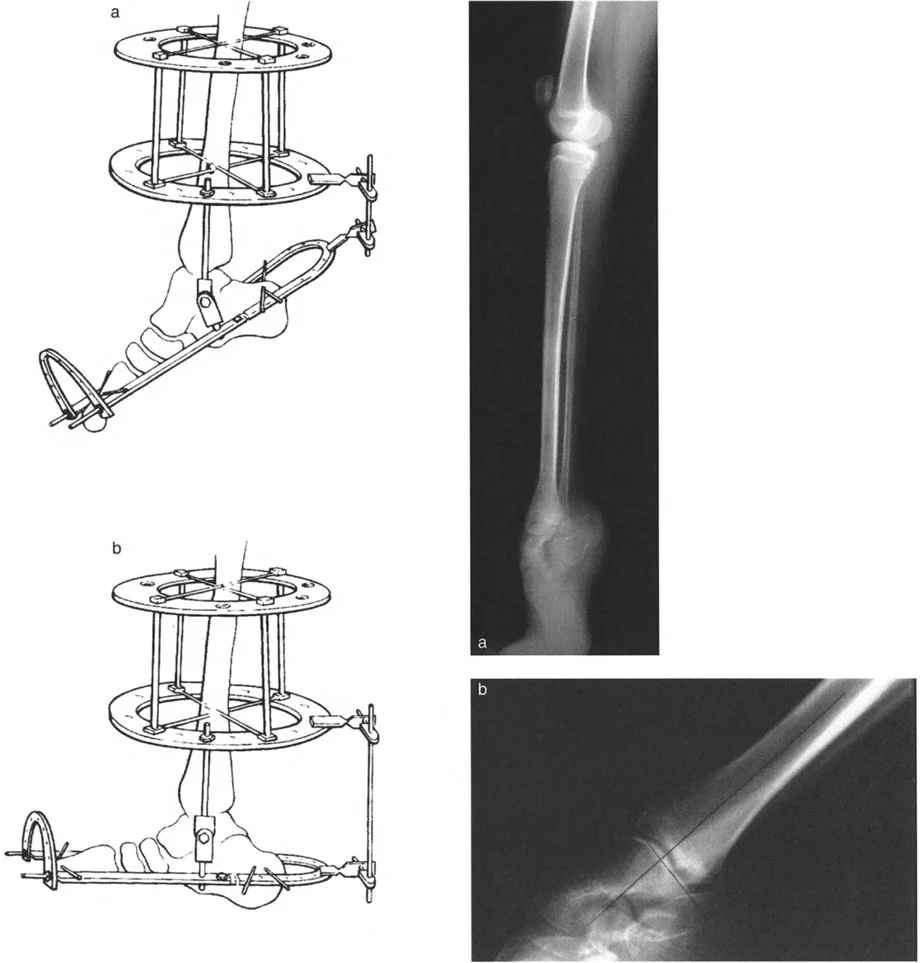

- صورة توضح تقلصًا في الكاحل بزاوية 20 درجة.

- صورة شعاعية توضح تقلصًا في الكاحل بزاوية 20 درجة.

زاوية الكاحل الظهرية الظنبوبية (ADTA)

تُستخدم زاوية الكاحل الظهرية الظنبوبية (ADTA) كمعيار تشخيصي مهم لتقييم مدى تقوس الكاحل. وهي تقيس الزاوية بين محور عظم الظنبوب ومستوى عظم الكاحل. في الوضع الطبيعي، تسمح هذه الزاوية بحركة كافية لثني القدم للأعلى. أي انحراف عن هذه الزاوية الطبيعية يمكن أن يشير إلى وجود تقوس أو تشوه.

- تقوس الظنبوب البعيد (Procurvatum of Distal Tibia): في هذه الحالة، يكون هناك انحناء غير طبيعي في الجزء السفلي من عظم الظنبوب، مما يمنع عظم الكاحل من الثني للأعلى بشكل طبيعي بسبب اصطدامه بالظنبوب.

- عظم الكاحل المسطح (Flattop Talus): يحدث هذا عندما يكون الجزء العلوي من عظم الكاحل مسطحًا بدلاً من شكله المستدير الطبيعي، مما يؤدي إلى اصطدامه بعظم الظنبوب عند محاولة ثني القدم للأعلى.